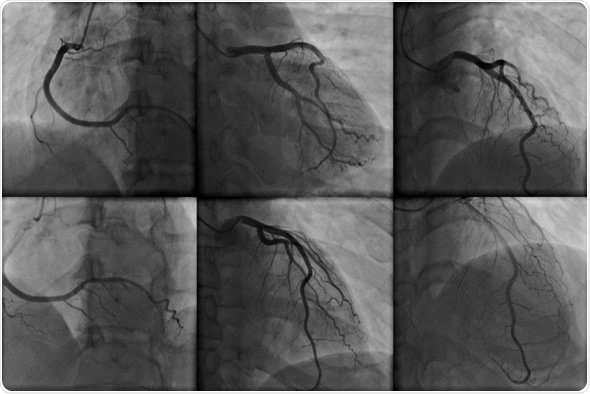

Coronary angiography - Image Copyright: kalewa / Shutterstock

• Coronary angiography visualizes the inside of the coronary arteries. These images can locate stenoses in the arteries that may be responsible for chest pain, and which could cause a heart attack.